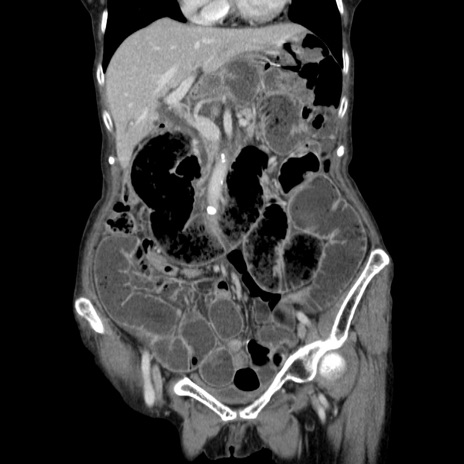

症例25(冠状断像)

【症例】80歳代女性

【主訴】胸のつかえ感

【現病歴】約9時間前に食後から胸のつかえた感じあり、嘔吐あり、来院。

【既往歴】胃癌(全摘)、胆摘、虫垂炎

【身体所見】心窩部に圧痛あり、反跳痛なし。

【データ】WBC 5700、CRP 0.05